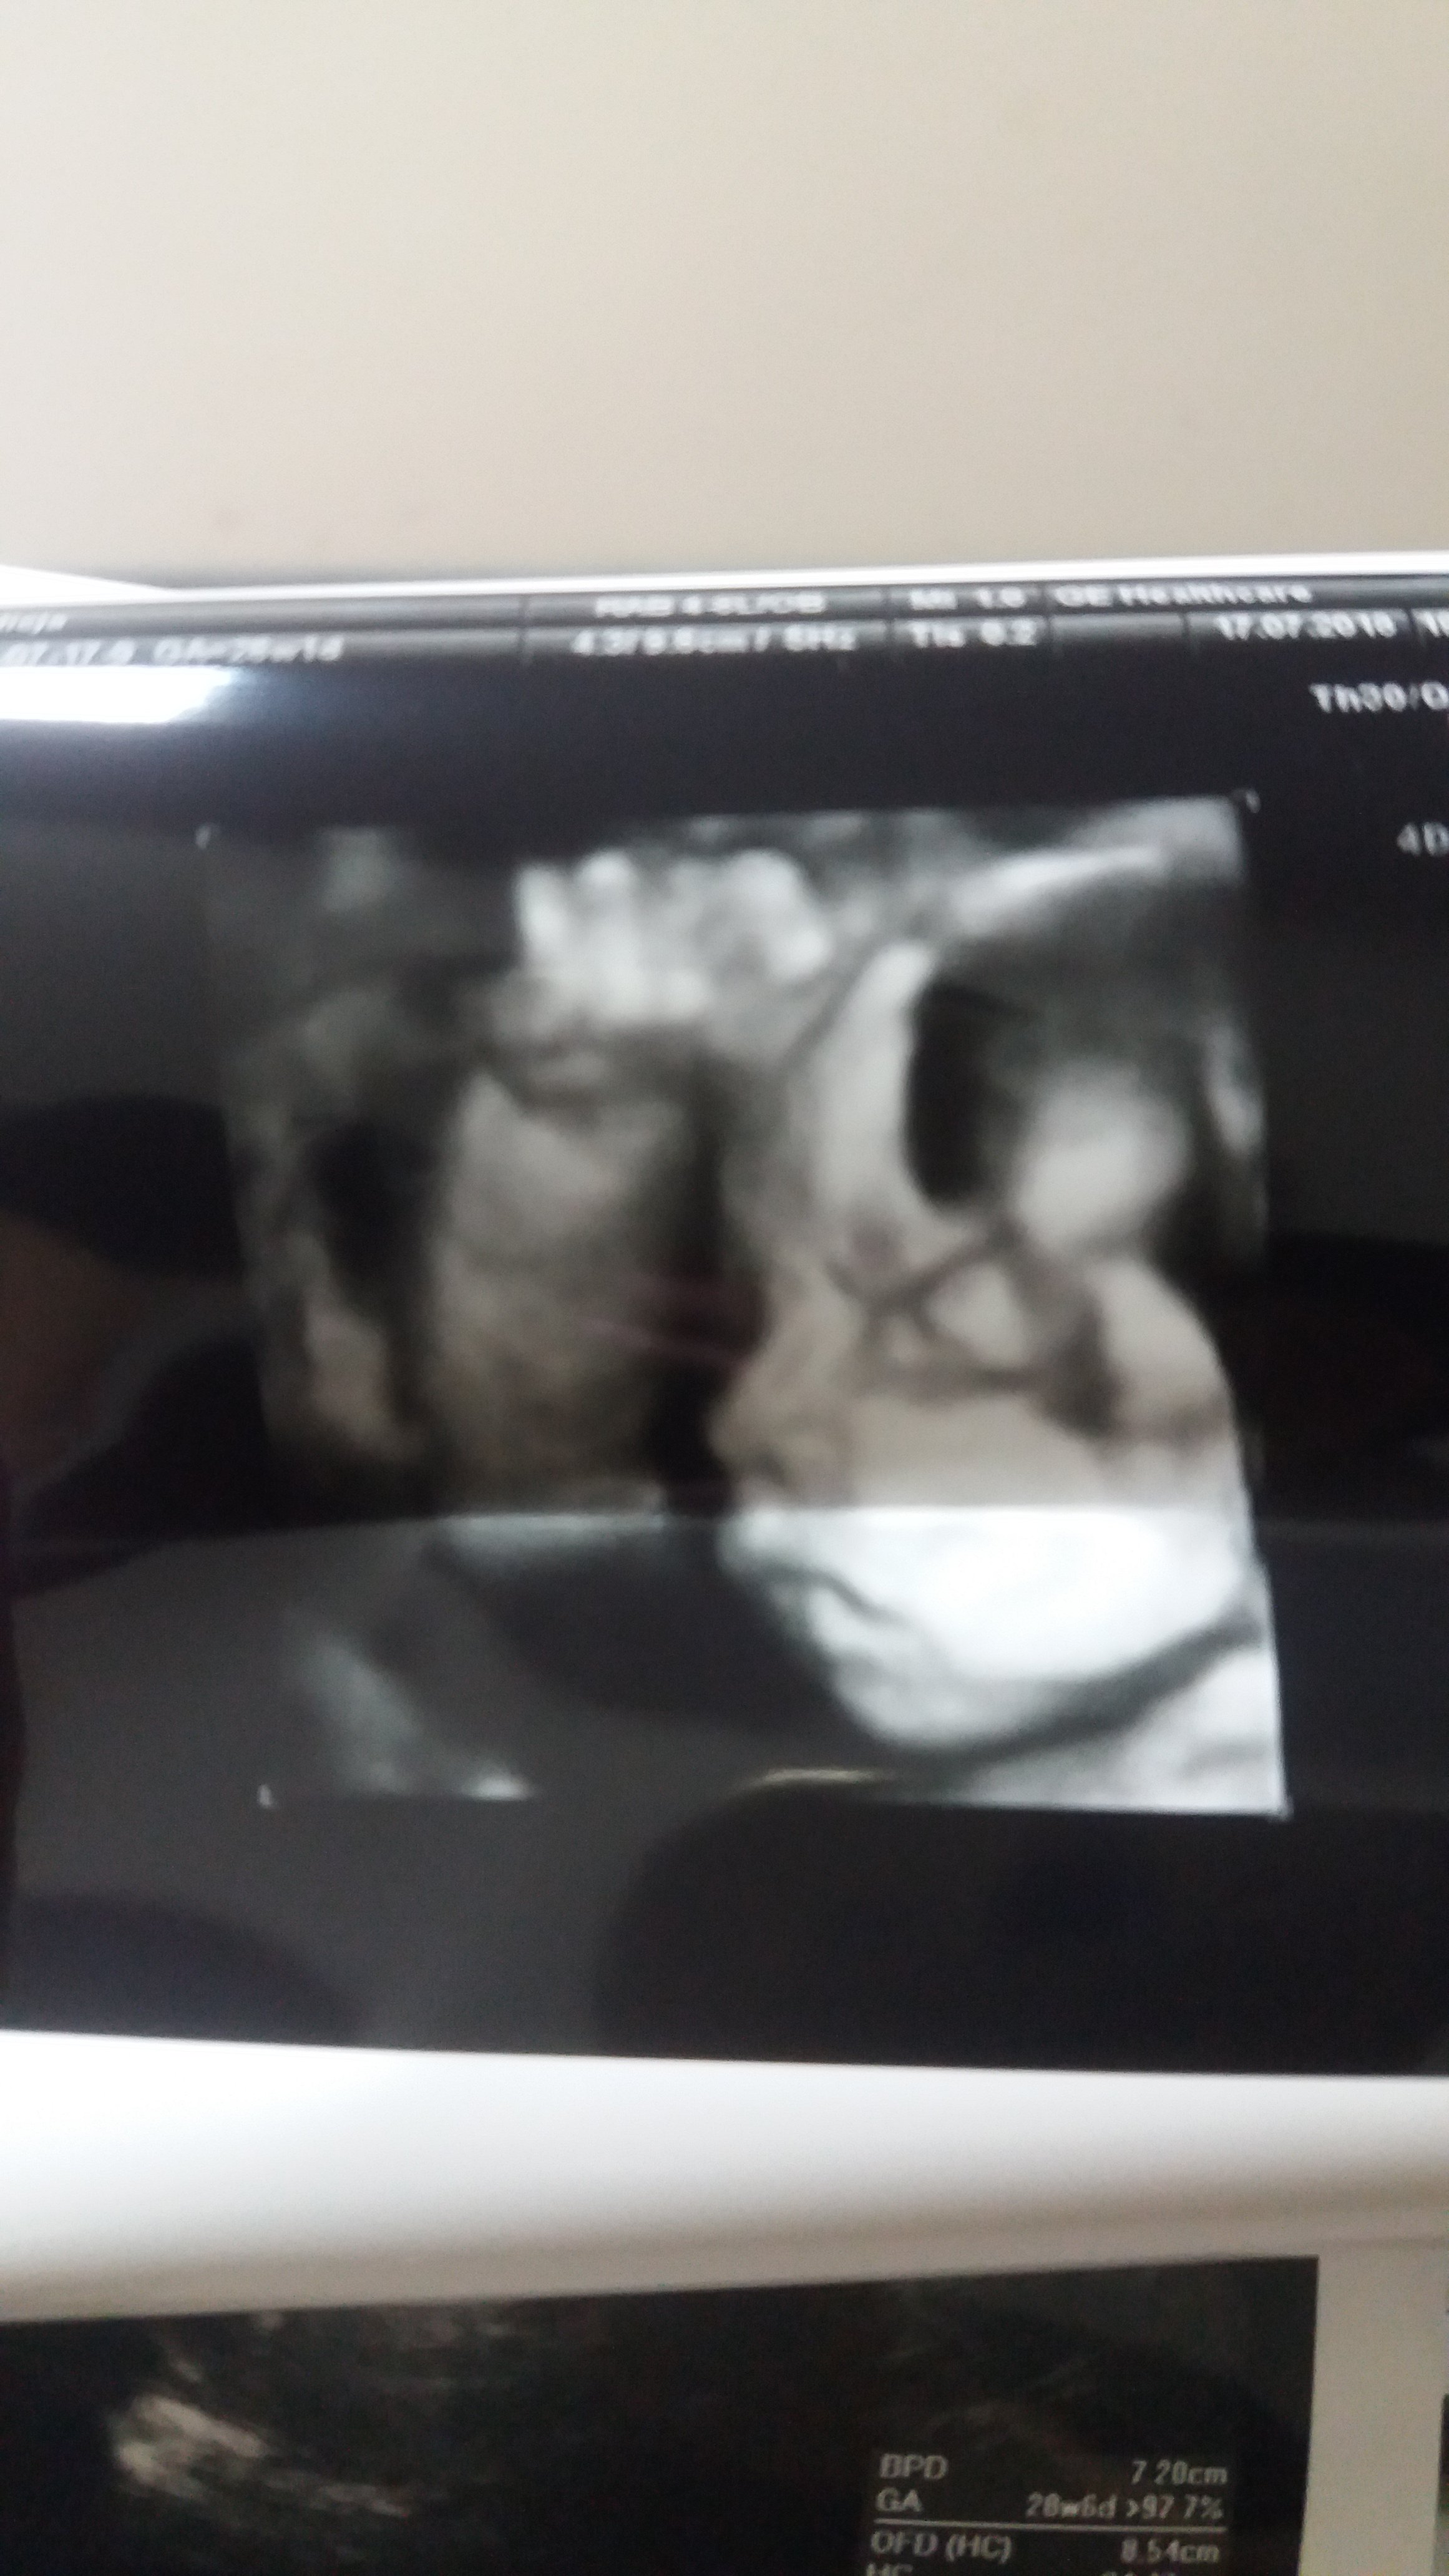

Ja dziś byłam na szybkim 4d :) mała wazy 1.091 kg i chyba bardziej podobna do tatusia póki co ale to wszystko moze się zmienić :) najważniejsze że po mamusi jest od pasa w dół i już nic się w tym względzie nie zmieni ;)

Załączniki

• 20180717_184350.jpg

20180717_184350.jpg

854,8 KB · Wyświetleń: 156